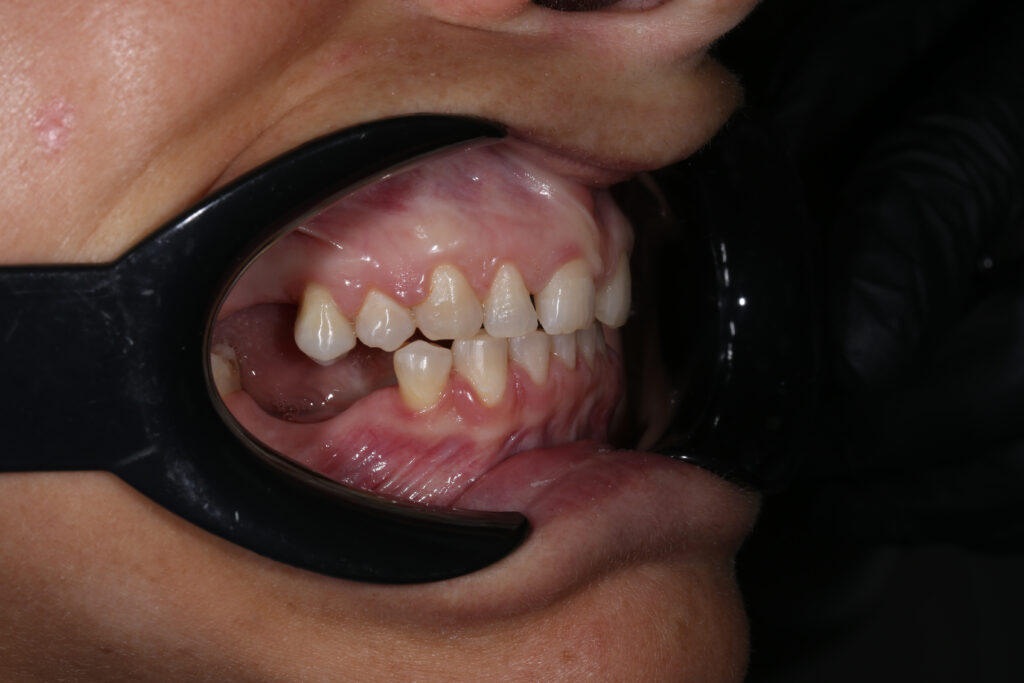

Результаты ортодонтической части

Была установлена брекет-система Damon Q. Срок лечения брекетами составил 11 месяцев.